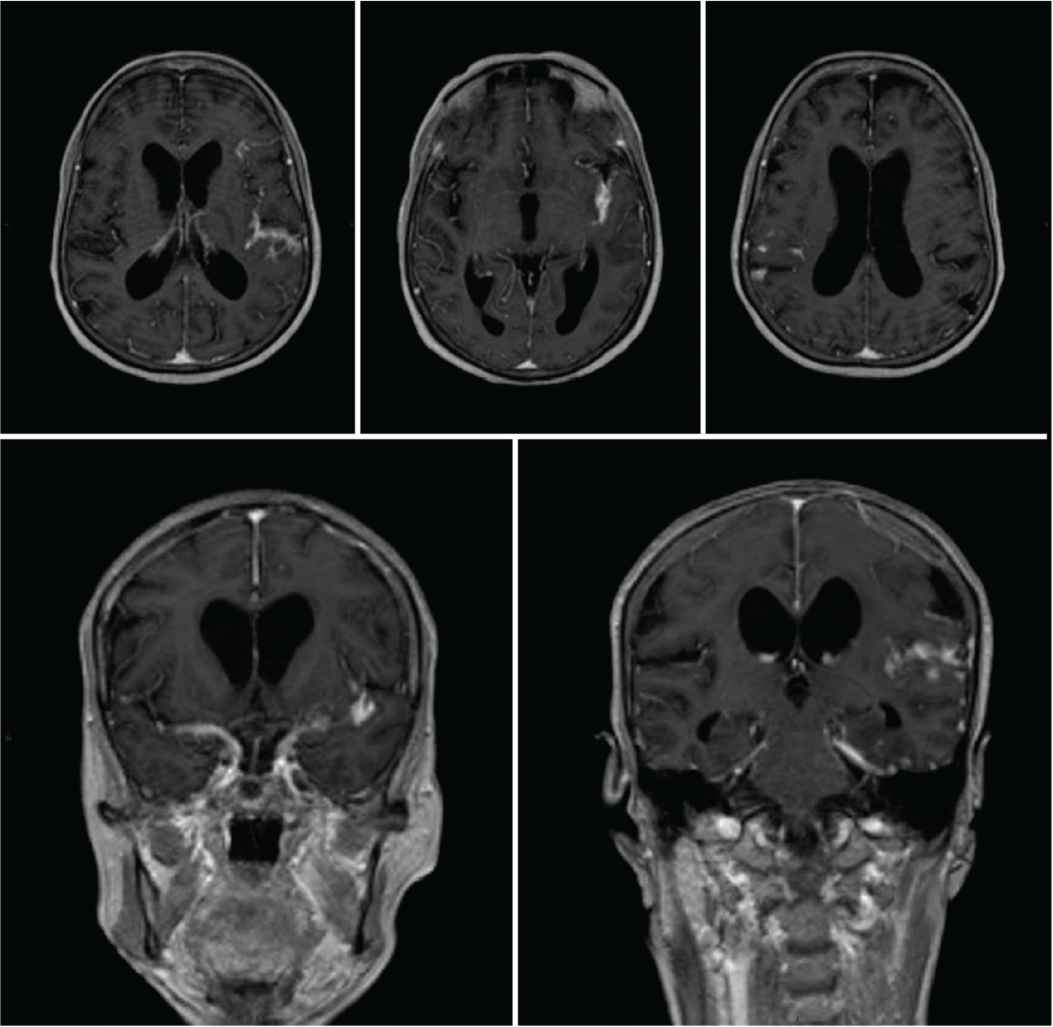

A 60-year-old female presented to the emergency department with headache, neck pain, and low back pain that started 6 months ago. Two weeks prior to presentation, she had difficulty walking with no sphincter control disturbance or sensory symptoms. She had no history of diabetes mellitus, infectious disease, or dyslipidemia. She is a housewife who is married and living with her children. Although no family history of tuberculosis was documented, she gave a strong history of contact with a patient who has open pulmonary tuberculosis that was not on treatment. Her systemic examination was normal including vital signs, lung auscultation, cardiac examination, and skin inspection. As part of her investigations, she had normal complete blood count, renal and liver function tests, and electrolytes including sodium, magnesium, and phosphate. Her erythrocyte sedimentation rate was high at 64. The result of her human immunodeficiency virus test was negative, and the chest X-ray was normal. Magnetic Resonance Imaging (MRI) of the whole spine revealed intramedullary dorsal (thoracic) ring-enhancing lesion at the level of T10–T11 (Figure 1). MRI of the brain showed diffuse meningeal enhancement with no intraparenchymal cerebral or cerebellar lesions (Figure 2). Cerebrospinal Fluid (CSF) analysis revealed a lymphocytic pleocytosis with a leukocyte count of 90 cells (reference range, 0–5), lymphocyte predominance (87%), raised protein of 236 mg/dL (reference range, 15–60 mg/100 mL), low CSF glucose 18 mg/dL (reference range, 50–80 mg/100 mL). CSF Gram stain, culture, and sensitivity were negative for all bacteria including mycobacterium tuberculosis. In addition, the Polymerase Chain Reaction (PCR) for viral, bacterial, and mycobacterial DNA was negative. Unfortunately, and despite tuberculous meningitis being the most likely diagnosis based on clinical and paraclinical data, the patient was not started on antituberculous medications. The treating infectious diseases consultant requested a brain and meningeal biopsy, which was declined by the patient’s family. The consultant refused to start the patient on antituberculous medications if no tissue is obtained for pathological confirmation of diagnosis. The patient’s condition deteriorated, and she was admitted to the intensive care unit with intubation and mechanical ventilation. The patient developed status epilepticus and was started on levetiracetam 1000 mg twice daily. She developed focal neurological deficits and multiple cranial nerve involvement. A repeated MRI of the brain showed an acute ischemic infarction with restricted left capsular, medial temporal, and hippocampal lesions in the apparent diffusion coefficient map (Figure 3). It also revealed persistence and even worsening of meningeal enhancement. Repeated CSF analysis revealed low glucose at 8, high protein at 255, and white blood cells count of 190 with lymphocytes (85%) and neutrophils (15%). Owing to the family request (based on neurology team recommendation) as well as clinical and radiological deterioration, the patient was started on antituberculous medications (rifampicin 600 mg, isoniazid 300 mg, pyrazinamide 1500 mg, and ethambutol 1200 mg) and oral corticosteroids through a nasogastric tube. This was several weeks after admission to the intensive care unit. Despite the advanced stage of the disease, the development of endarteritis obliterans with multiple ischemic strokes, and poor clinical condition, the patient’s condition improved, and her seizures stopped. Her neurological status improved, and she became more alert with better power in all limbs, and after 3 weeks, she was weaned off ventilation and was extubated. The patient was transferred to a rehabilitation center for an aggressive physiotherapy regimen, and the family was instructed to continue the antituberculous medications for a full 12-month period. Unfortunately, the patient died from neurological complications related to tuberculous meningitis (multiple infarcts with superadded massive pulmonary embolism).

Magnetic Resonance Imaging (MRI) scan of the brain showing diffuse meningeal enhancement with no intraparenchymal cerebral or cerebellar lesions.